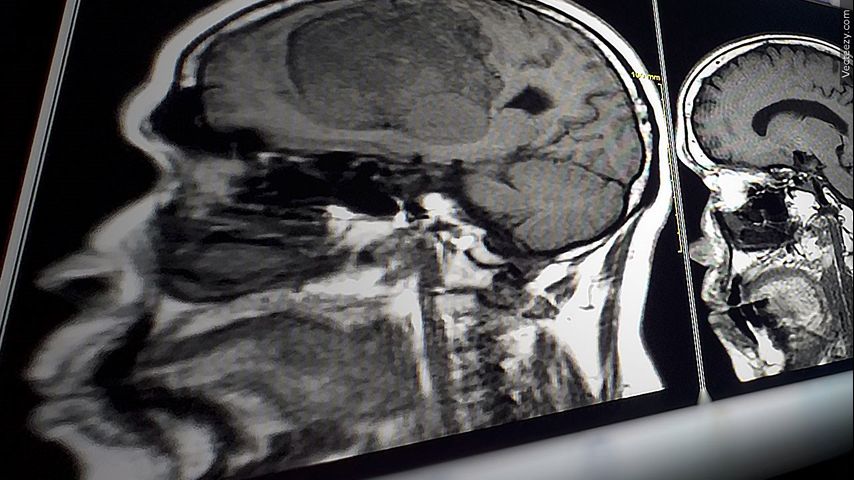

BATON ROUGE — Brain aneurysms affect millions of people, nearly seven million people in the United States are living with unruptured aneurysms.

A brain aneurysm is a weak spot in a blood vessel that bulges out. If it bursts, it can cause dangerous bleeding within the brain.

"That's usually done with an MRI of the blood vessels called an MRI angiogram," Dr. Fox said.